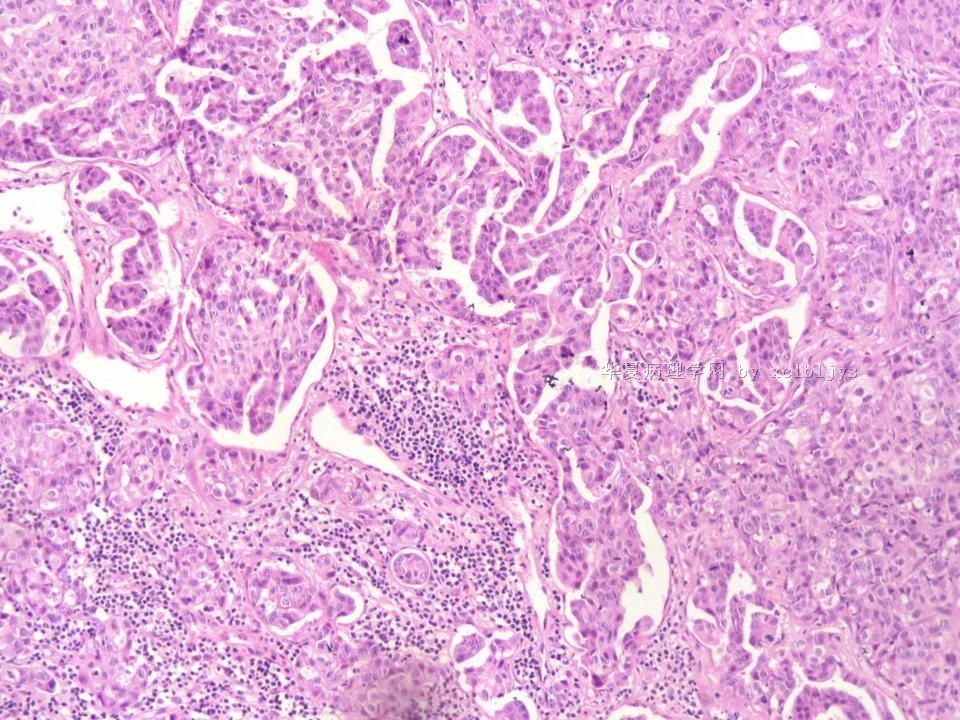

姓    名: ××× 性别:  男 年龄:  56

左锁骨上肿块三月余,手术切除。

蚕豆大肿块,包膜较完整,切面灰红色,质软。

• 左锁骨上肿块(IHC)图3

图3

转移癌

首先考虑甲状腺或肺来源

转移性腺癌。清查胃、肺等处有无原发灶。

转移性腺癌,请查消化道

免疫组化结果:TTF-1(+),CK7(+),CK20(-),TG(-)。临床近一步检查,肺未见肿块,左甲状腺发现肿块,目前仍未处理。

从形态结构看,有腺泡也有乳头结构,倾向转移性肺腺癌。